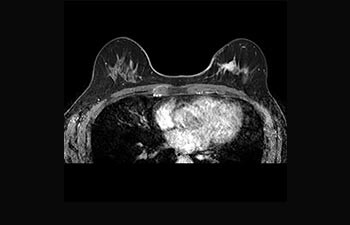

La Sra. Silvia Schiffer, directora y radióloga experta en la clínica Radiologie Schiffer, en Alemania, comparte sus experiencias con el sistema de RM Prodiva 1.5T.

Conozca la opinión de los primeros usuarios de Ingenia Prodiva 1.5T acerca de sus experiencias con el sistema y cómo influye este en su centro de diagnóstico por imagen.